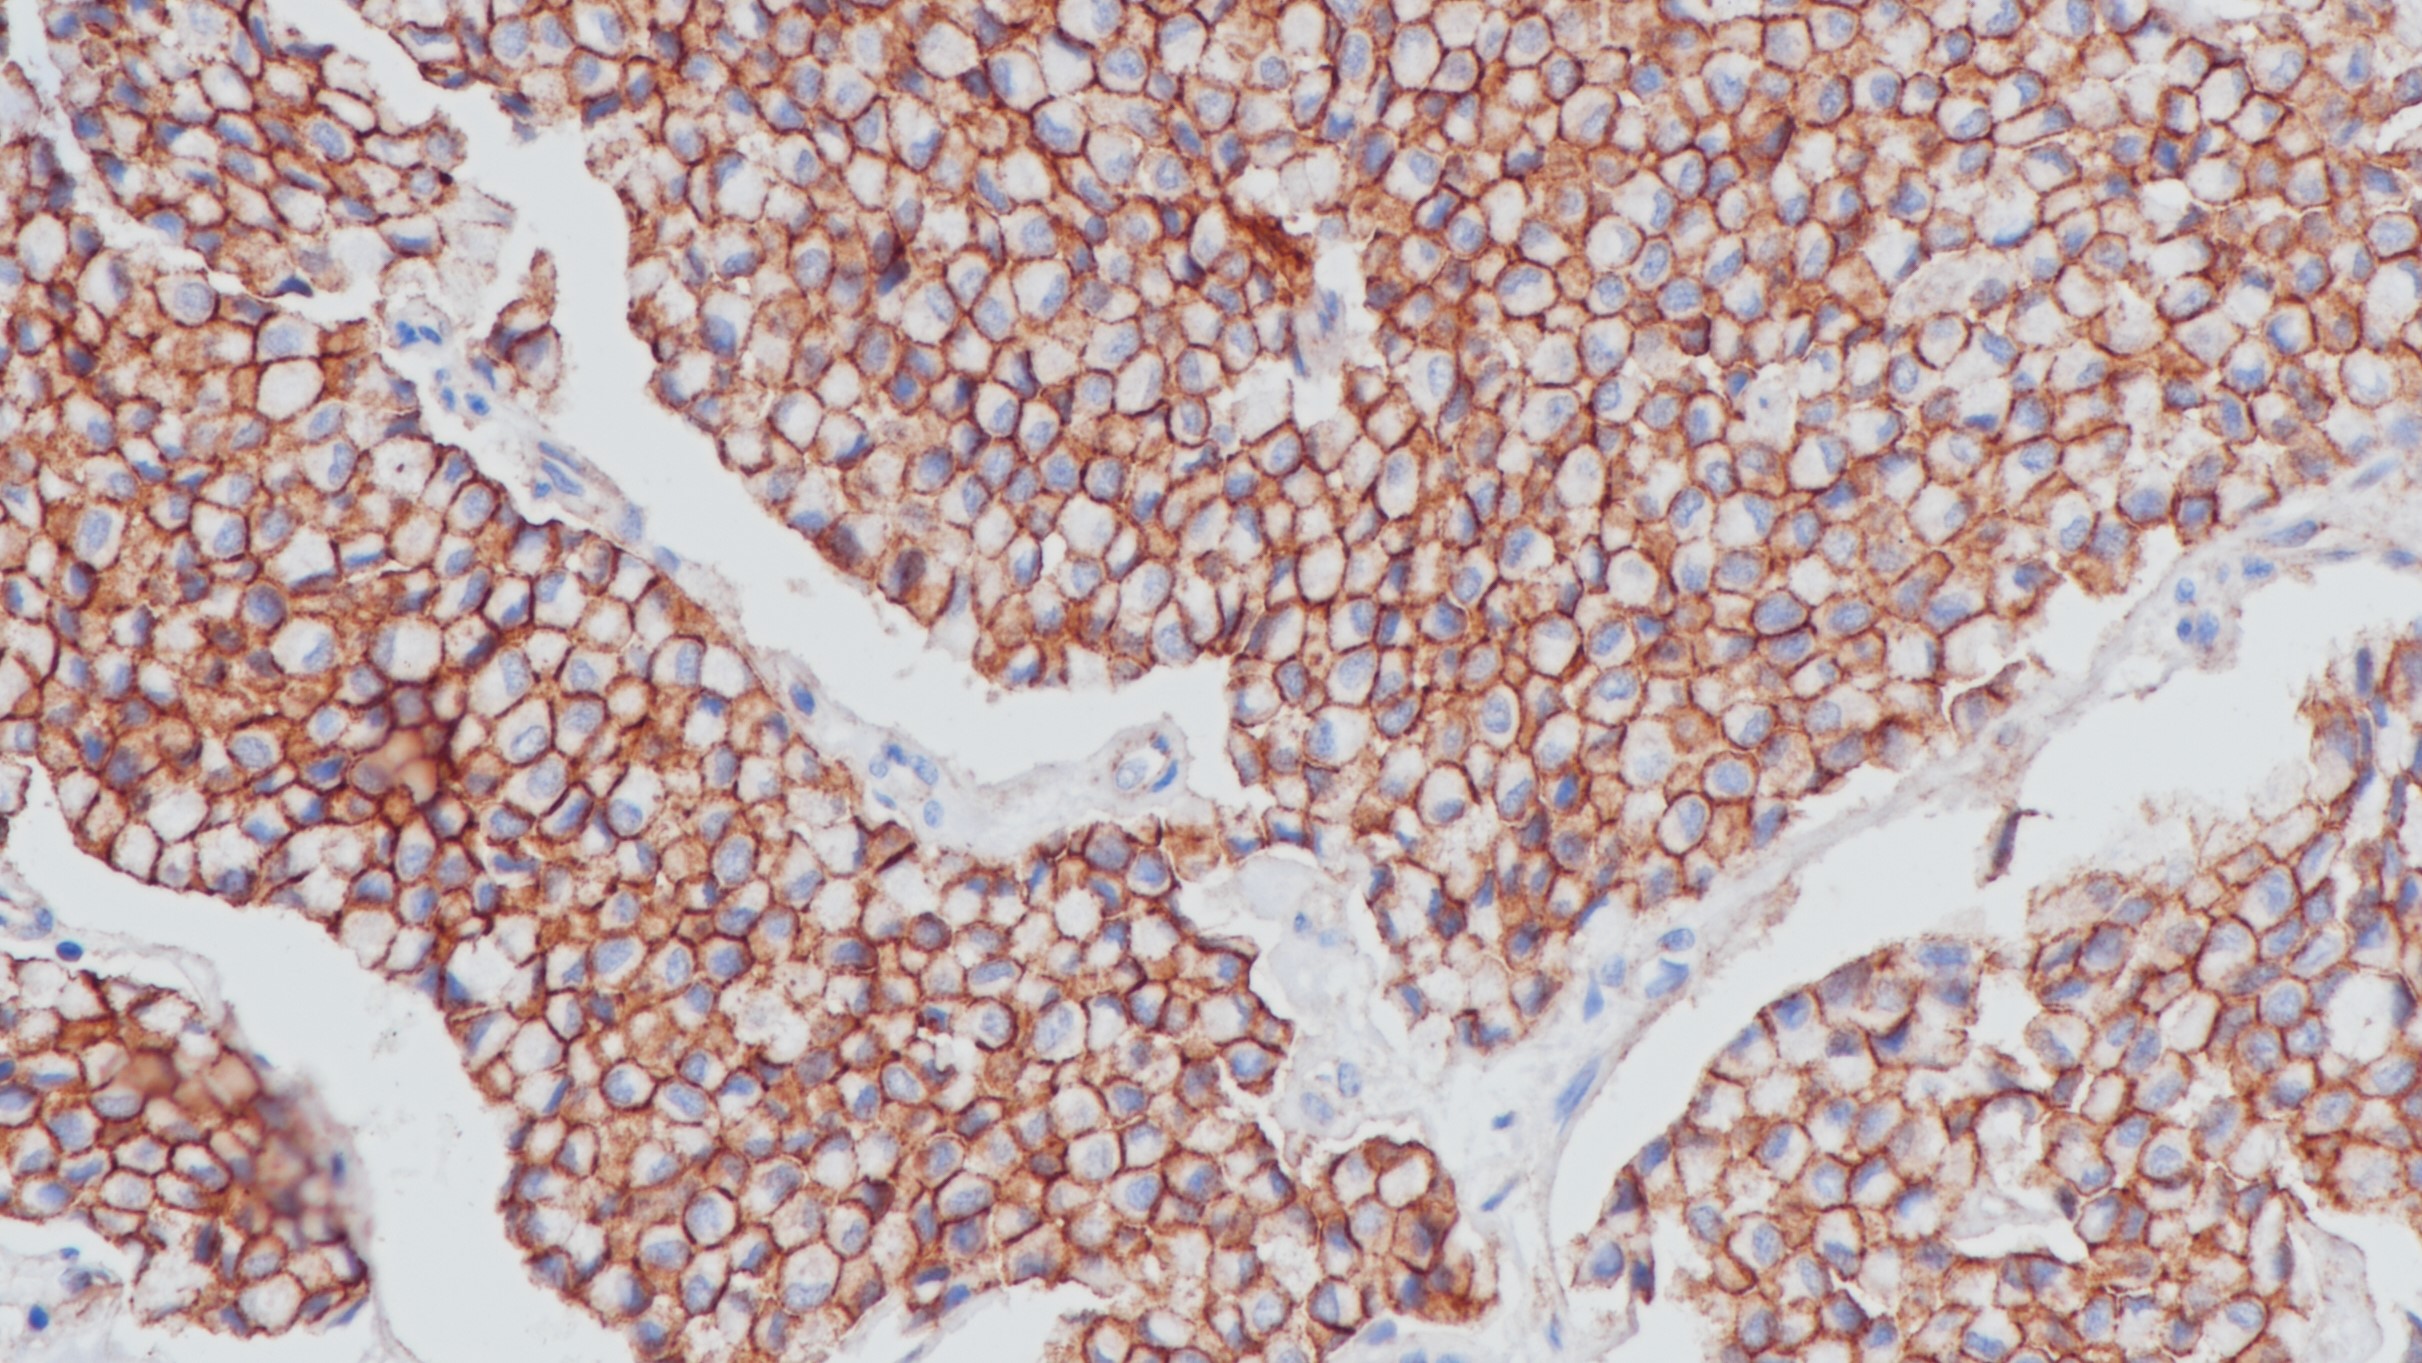

2.Pathology & Oncology Research: Official Journal of the Arányi Lajos Foundation, 2020, Vol.26 (1), pp.533-539